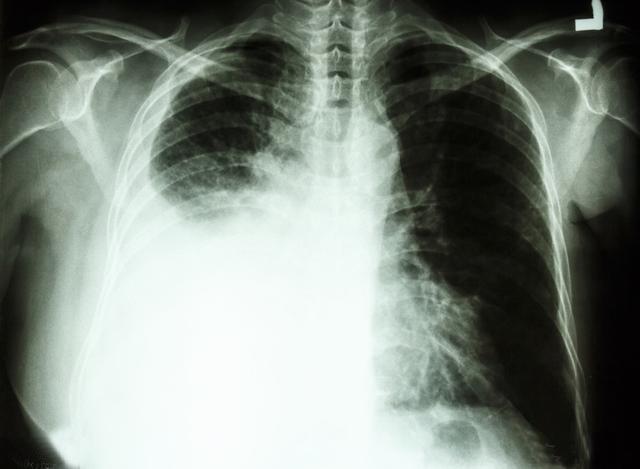

肺类癌属于少见性肿瘤,约占肺部肿瘤的1%-2%,占全部类癌的10.2%~11.5%,分中央型类癌和周围型类癌两种。肺类癌起源于支气管肺粘膜及粘膜下腺体的嗜银细胞,即Kulchitsky细胞。这些细胞浆内有神经内分泌颗粒,具有分泌功能。由于类癌属于神经内分泌肿瘤,有些文献报道部分类癌可以出现类癌综合症症状,表现为阵发性皮肤潮红、腹泻、哮喘、心动过速、面部充血、血压波动和紫绀,但出现此症状的病例较少,病人也可出现非特征性症状,例如胸痛、发热。

据报道,类癌患者的年龄幅度较大,可从10岁~83岁,中位年龄为45岁。临床根据类癌的生物学行为分为:分化较好的典型类癌和有侵袭性的不典型类癌,典型类癌占多数,非典型类癌仅占11.4%。典型性类癌预后较好,即使伴有同侧纵隔淋巴结转移,5、10和15年生存率分别为92%、88%、76%,而侵袭性不典型类癌的预后较差,5年和10年生存率分别为69%和24%~52%。预后与临床分期及淋巴结转移相关。典型类癌的平均年龄比非典型类癌要年轻10岁,而且它是儿童期最常见的肺部恶性肿瘤。类癌中央型多于周围性,这是因为越靠近中心支气管,粘膜内的K细胞分布越多,发生类癌的机会越大。

CT上肺类癌较其他肺癌钙化更常见,在组织学上肺类癌钙化的发生率约为30%,中心型类癌可高达39%。肺类癌转移少见,中央型肺类癌病程长,进展缓慢,倍增时间长,预后相对较好。支气管镜及活检病理对肺类癌的确诊率低,需要进一步免疫组化检测综合判断。对疑似类癌综合征的患者进行24h尿5-羟吲哚(5-HIAA)水平测定,如5-HIAA升高对类癌诊断有一定帮助。由于典型肺类癌预后较好,术后一般不考虑化疗。对于非典型类癌,5年和10年生存率比较低,不管有没有淋巴结的转移,目前还是推荐术后化疗。由于对化疗的敏感性较低,晚期患者化疗有效率不高。